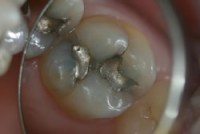

Amalgam mı? Hava, Cıva!

Ama Ama, Amalgam Çok Kötü Diyorlar? Son zamanlara kulağıma sık sık amalgam dolguların, yani “gümüş dolgu” tabir edilen metal renkli diş dolgularının sağlığa çok zararlı olduğuna dair haberler çalınıyor. Hatta sağlık açısından bu dolguların ağızdan sökülmesi veya sık sık yenilenmesi gerektiğinden bahsediliyor. Konunun ne kadarının doğru, ne kadarının tartışmalı olduğunu yerinde incelemek ve güncel bilgileri […]